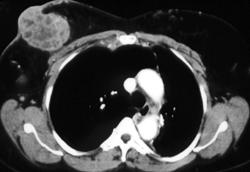

Mediastinal and Chest Wall Abscess